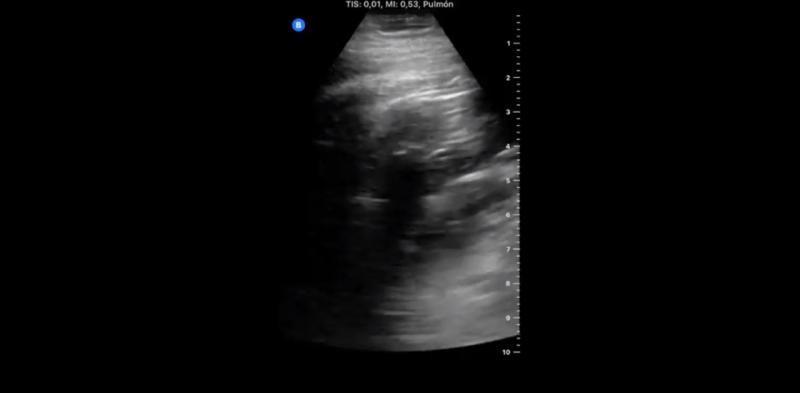

„Ziua 1 după ce am fost diagnosticat cu COVID-19. Durere în gât, durere de cap puternică, tuse seacă, dar fără dificultate respiratorie. Fără anormalități la plămâni, la ecografie”, a scris el, în primul astfel de mesaj.

Plămânii doctorului Yale Tung Chen, în prima zi după diagnosticul COVID-19.